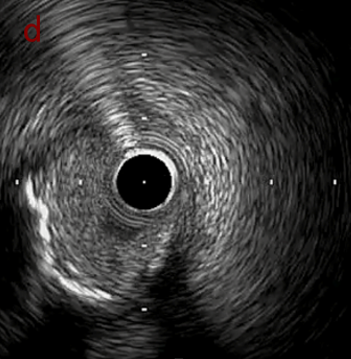

IVUS after OAS high speed 3回

IVUS imaging after high speed 3回

a,b,cはさらに石灰化に食い込み、石灰化量は減少。

それに伴いdではbiasがさらにtentingのIVUS所見にへんかしhigh injury riskと思われた。

引き続き造影で確認してpinpointで引きのOAS high speedを3回さらに追加のためcでIVUSマーキングを行い、その点より引きで赤線のpinpoint OAS high speedを行い、dに関してはinjury回避のためにOASを当てない方針とした。